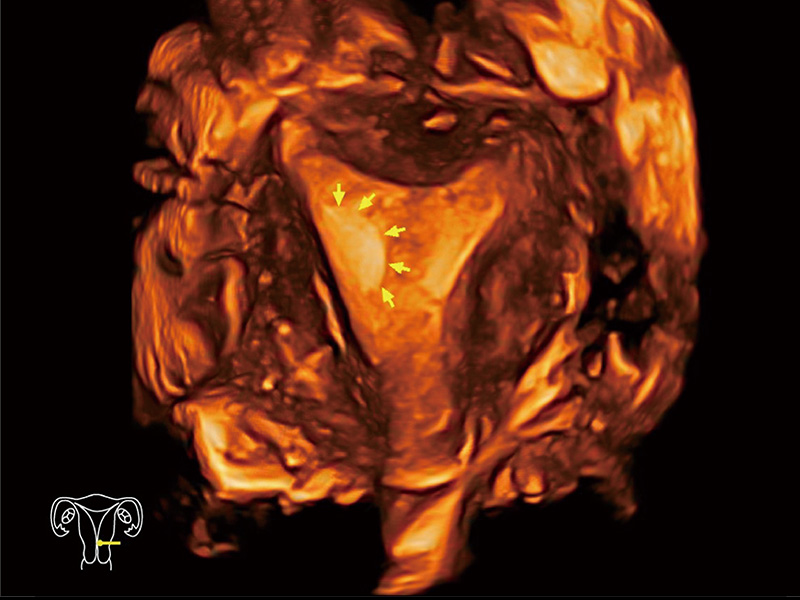

腔内三维成像技术获得显著提升,超大扇角在满足日常基础扫查的同时,支持卵泡自动测量及多种三维渲染模式,为您提供更多的诊断信息,尤其是在子宫畸形的诊断,内膜及肿瘤占位观测中起到了重要的作用。

中央型宫腔粘连